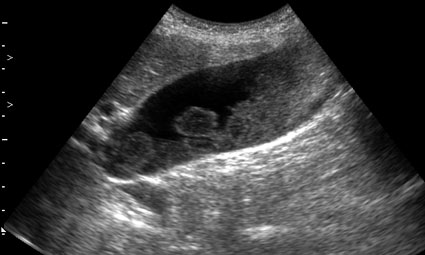

Женщина 59 лет с болями в подребрье справа.

Сонограмма желчного пузыря при поступлении в стационар.